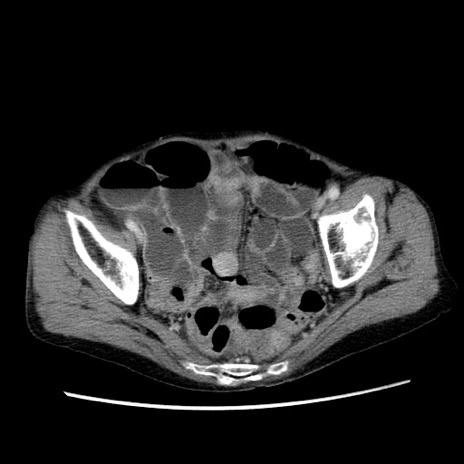

症例25(横断像)

【症例】80歳代女性

【主訴】胸のつかえ感

【現病歴】約9時間前に食後から胸のつかえた感じあり、嘔吐あり、来院。

【既往歴】胃癌(全摘)、胆摘、虫垂炎

【身体所見】心窩部に圧痛あり、反跳痛なし。

【データ】WBC 5700、CRP 0.05